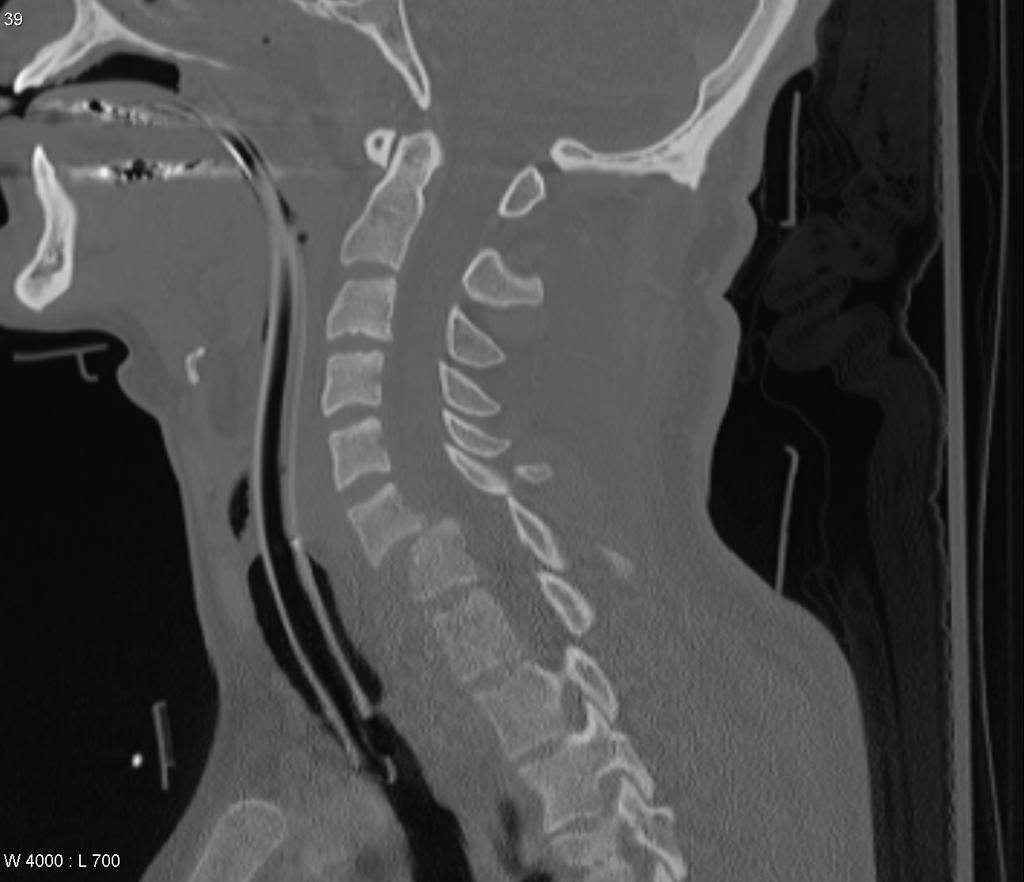

His CT show this: (Case courtesy of Dr Frank Gaillard, Radiopaedia.org)

Right Facets

Bilateral Facet Joint Dislocations C6/7